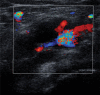

Cystic adventitial disease is a rare disorder that occurs in peripheral arteries. Calf claudication caused by compression of the popliteal artery is a typical presentation of this disease. This is a report of two cases of occluded popliteal artery decompression by percutaneous ultrasound-guided cyst aspiration. In both cases, decompression of the artery was achieved with a significant decrease in the size of adventitial cysts and restoration of flow. Both patients reported complete resolution of symptoms and no calf pain 5 years after the procedure. MR findings and resolution of symptoms in these two patients show the efficacy of percutaneous adventitial cyst aspiration in a 5-year follow-up.